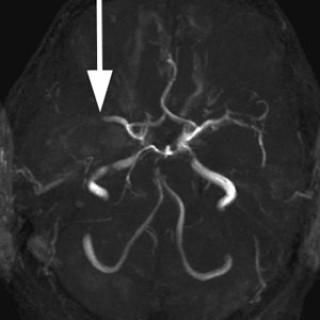

Den første detaljerte beskrivelsen av cerebral venetrombose, også kalt sinusvenetrombose, ble forfattet av Ribes i en artikkel fra 1825 (1). Siden fulgte en rekke kasuistikker basert på autopsimaterialer, som førte til den oppfatning at cerebral venetrombose representerte en sjelden, alvorlig sykdom karakterisert med hodepine, papillødem, epileptiske anfall, fokale utfall, progredierende koma og død (2, 3). Introduksjon av moderne nevroradiologisk utredning har gjort diagnostisering intra vitam mulig, dermed er det blitt klart at sykdomsutviklingen ved cerebral venetrombose heller sjelden er i...